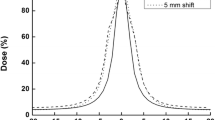

For each patient, six plans were generated, and the results were then divided into two sets. The first result set was VMAT at different MICs (MLCi2, Agility (FFF), and Agility (FF)), while the second set included corresponding IMRT results. The acceptance criteria achieved in all plans with VMAT and IMRT techniques depend on the PTVs and OARs. Figure 1A, B show the dose distribution for VMAT and IMRT plans with different MLC designs for PTV60 and PTV44. Also, Fig. 2A, B reveal the PTV60 DVH of VMAT and IMRT with different MLC. Additionally, Tables 2, 3 summarize the dosimetric DVH parameters of the PTVs and OARs with different MLC types for VMAT plans.

Regarding PTV60, the results revealed that there were no significant differences for D2% between VMAT techniques with different MLC types (MLCi2, Agility FFF and Agility FF). The remaining parameters (D98%, D95%, D50%, Dmin and Dmean) showed no significant difference between Agility FF and FFF. In contrast, there were statistically significant differences between Agility (FFF and FF) and MLCi2, as shown in Table 2. The results also revealed that CI and HI had the optimal values for Agility FF (0.89, 0.09) and FFF (0.85, 0.095) compared with MLCi2 (0.78, 0.11), respectively (Table 2). There were statistically significant differences between Agility (FFF and FF) and MLCi2 for CI and HI.

Tables 5, 6 summarize the results of the second set off PTVs and OAR dosimetric parameters for the IMRT technique. For PTV60, the results revealed that there were no significant differences in D2% of Agility FF, FFF, and MLCi2, but that the values of D98%, D95%, D50%, and Dmean showed a significant difference in Agility FF and FFF compared to MLCi2. The PTV60 values of CI and HI for Agility FF and FFF were better than those of MLCi2 obtained with IMRT plans, but no significant differences were found between Agility FF and FFF.